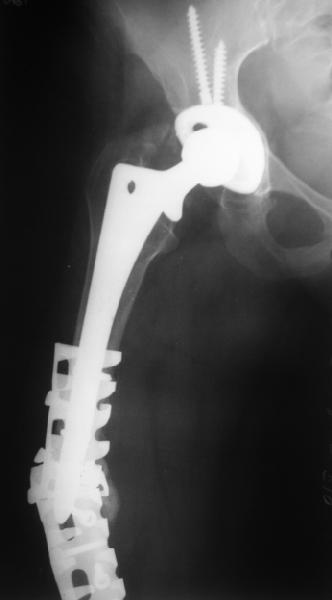

Female, rheumatoid, THA in 2003, car accident in 2006, failed plating. Nailing in Oct 2007. The nail is solid with hollow proximal part where the stem is docked. Last images are in 1 year after

nailing.